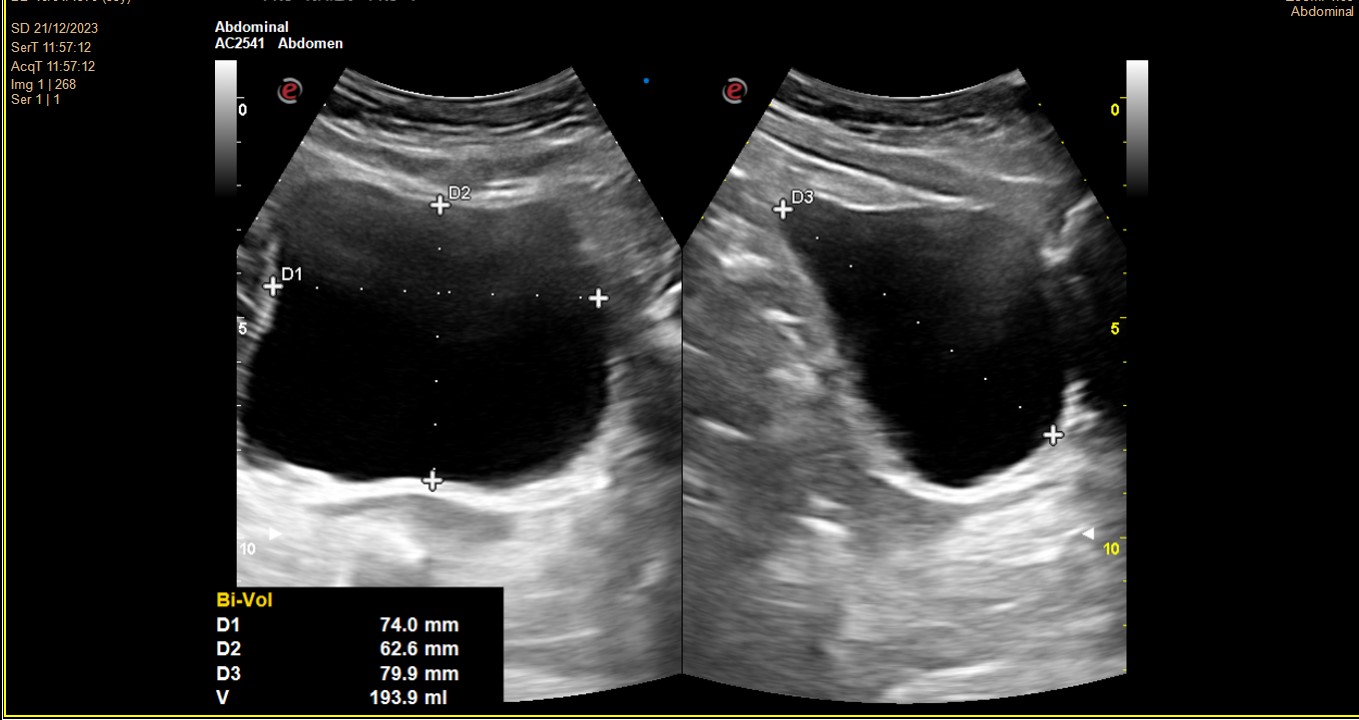

Dolor y nàuseas controladas con metamizol, come poco. Mal control glucémico. FG 87.7, Creatinina: 0,78, Urea 41,3. Pido estudio orina y función renal + ECOAP urinària en consulta: imagen hidronefrosis grado 4 RD vs imágenes anecoicas múltiples sin contenido, limites conservados pero desestructurades.

Derivación UHR (contacto telefónico). Ecografía Rx hospital. RD: Ecoestructura heterogénea. Diferenciación corticomedular alterada. Alteración morfológica. Dilatación hidronefrosi grau IV. No aumento de vascularización. RI: No se observan alteraciones.